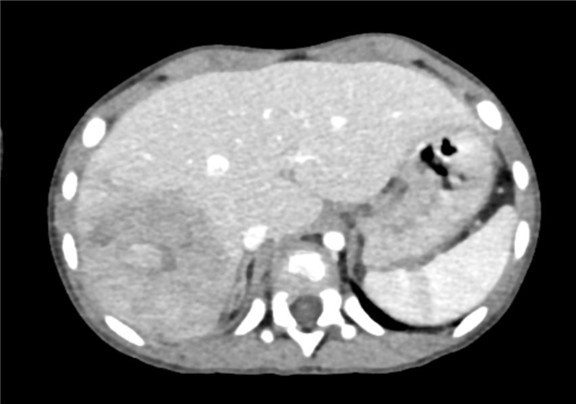

下腹部增强CT示:肝右叶较大肿块影,考虑恶性肿瘤(肝母细胞瘤)可能性大,较前减小

术前CT检查:

动脉期

静脉期